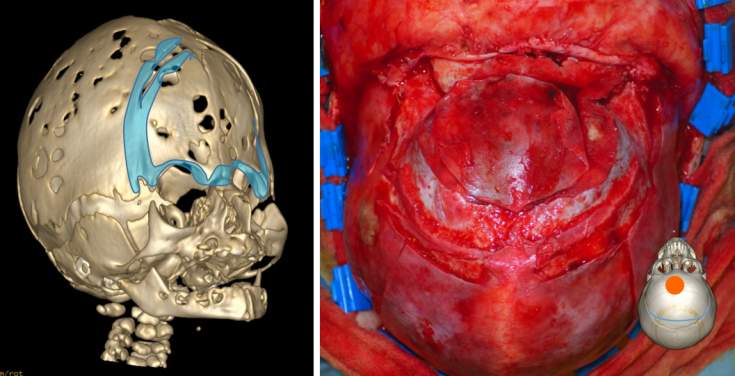

la décompression antérieure par craniectomie péri-frontale

est souvent le premier traitement lorsqu’il existe une compression cérébrale dès la naissance.

la cranioplastie avec bandeau fronto-orbitaire

est indiquée si on peut attendre l’âge de quelques mois, elle présente l’avantage de permettre dans le même temps une distraction cranio-faciale pour traiter une faciosténose lorsqu’elle est présente.

la décompression postérieure

peut être indiquée surtout en cas d’engagement tonsillaire symptomatique et de compression des sinus veineux.